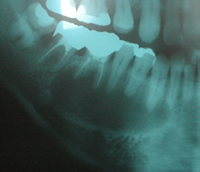

歯根嚢胞

※写真をクリックすると大きい画像が開きます。